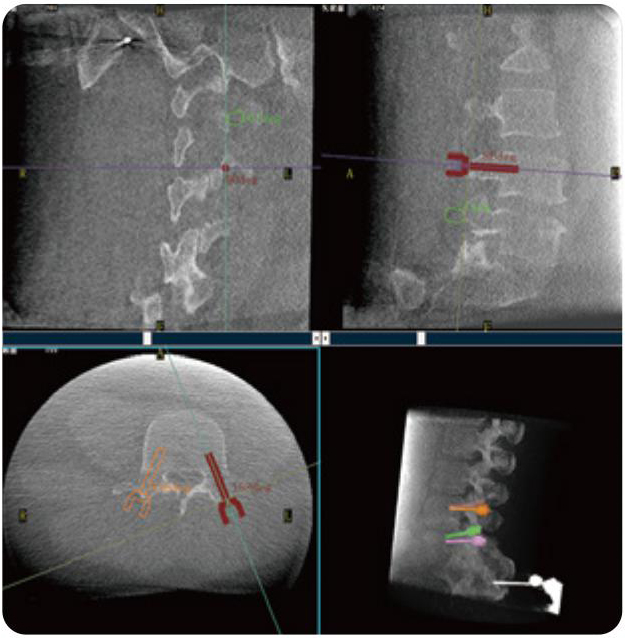

PL300B可應(yīng)用于多節(jié)段脊柱外科手術(shù),輔助醫(yī)生定位病灶部位,為脊柱外科手術(shù)(經(jīng)皮椎體成形術(shù)、椎弓根螺釘內(nèi)固定術(shù)等術(shù)式)提供術(shù)前手術(shù)流程規(guī)劃、入釘位置、角度可視化引導(dǎo),模擬仿真入釘輔助。

PL300B搭配普愛醫(yī)療自主研發(fā)生產(chǎn)的平板3D C形臂,借助一體化自適應(yīng)配準(zhǔn)( 軌跡配準(zhǔn))技術(shù),通過追蹤C(jī)形臂三維采集軌跡,自動(dòng)完成圖像坐標(biāo)建立和系統(tǒng)坐標(biāo)配準(zhǔn)。配準(zhǔn)精度更高,操作步驟少,系統(tǒng)運(yùn)作效率高。